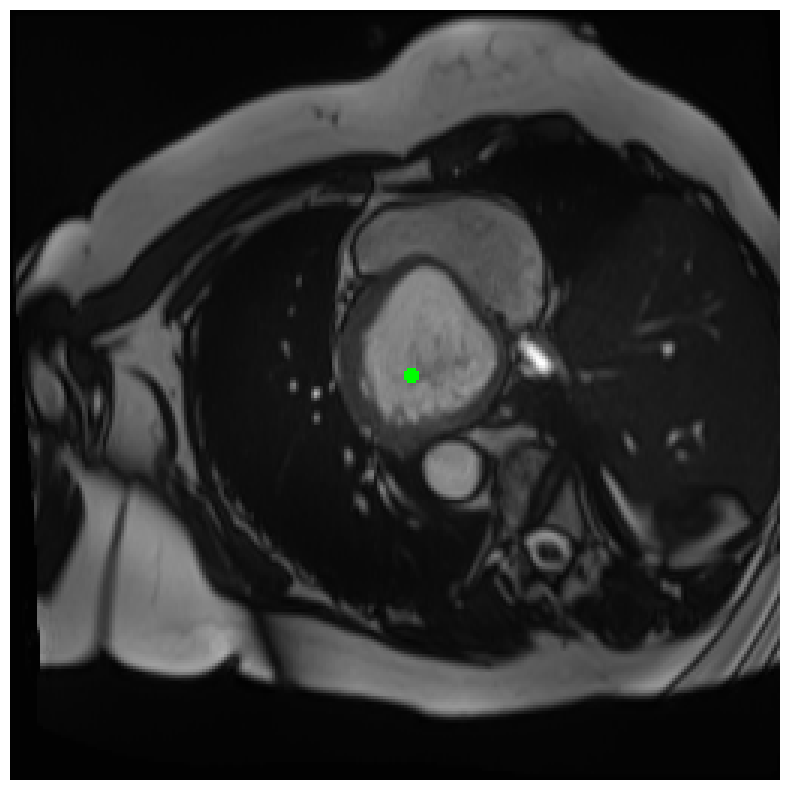

Generally, given an exact, full annotation of an object, such a Euclidean signed distance map encodes also information on the shape of an object. But when using a weak ground truth , where and , inferring a correct extent and shape of the objects is nontrivial. As shown in 1(b), Euclidean distance calculated from a point label source grows radially, regardless of the actual shape of the object, and thus makes little sense from an information point of view. Under the assumption of intra-object homogeneity and inter-object contrast (w.r.t intensities), this problem can be circumvented to a degree by using a distance function that takes also intensity values into account. An example of a commonly used distance measure with an intensity component is the Geodesic distance ([34]). Let denote a path between , with and being neighbors under a chosen adjacency relation. Reusing the notation from before, a Geodesic distance map from the boundary of the ground truth class , , can be defined as

Both the Intensity and the Minimum barrier distance are defined exclusively on the image intensity space. However, from the examples of distance map in 1(d), we can notice that the values still increase somewhat radially from the annotation. This behaviour is similar to the one of the Geodesic distance in 1(c) (which actually includes the spatial proximity in its definition), and is due to the summing operator in the general Geodesic distance definition in Equation 3. While the intensities of two neighboring pixels on a path may be the same, that will rarely be the case in real life, noise riddled images. This makes the Intensity distance function approximately monotonically increasing with increasing length of the path (in space), even on paths where the intensity is mildly fluctuating (e.g. consider a path with even pixels intensity value of and odd pixels intensity value of ). One could thus argue that such a definition of a distance, despite being based exclusively on intensities, is still capable of loosely encoding the spatial distance information.

On the other hand, while we can see that the MBD based maps are similar to Geodesic and Intensity ones (1(e)) with respect to the object shape recovery, they have a less pronounced and smooth increase in the values outward from the source point.

In contrast to Euclidean distance, the Geodesic, Intensity and Minimum barrier distance maps all encode contrast sensitivity and preserve the object structures by harnessing the intensity information of the underlying image. This holds even when calculated from point sources. In practice, using such maps for network training could mean a lower penalty for false positives that occur farther from the point annotation but are close to it in intensity. Thus still enabling the propagation of a sort of shape information (as it can be inferred from the raw image intensities).

We normalize the volumes and resize the slices to pixels. As the official dataset comes with full annotations, we create a synthetic point ground truth. This is done by first randomly choosing the centers of the point annotations within the class masks, followed by filling an ellipse with axes lengths of and (in pixels) around each center. The intersections of these elliptic discs with the underlying full annotations are then used as our point ground truth. See Figure 2 for an example of the created weak annotation mask. The point annotations are created for every slice, one for each foreground object present in the slice.